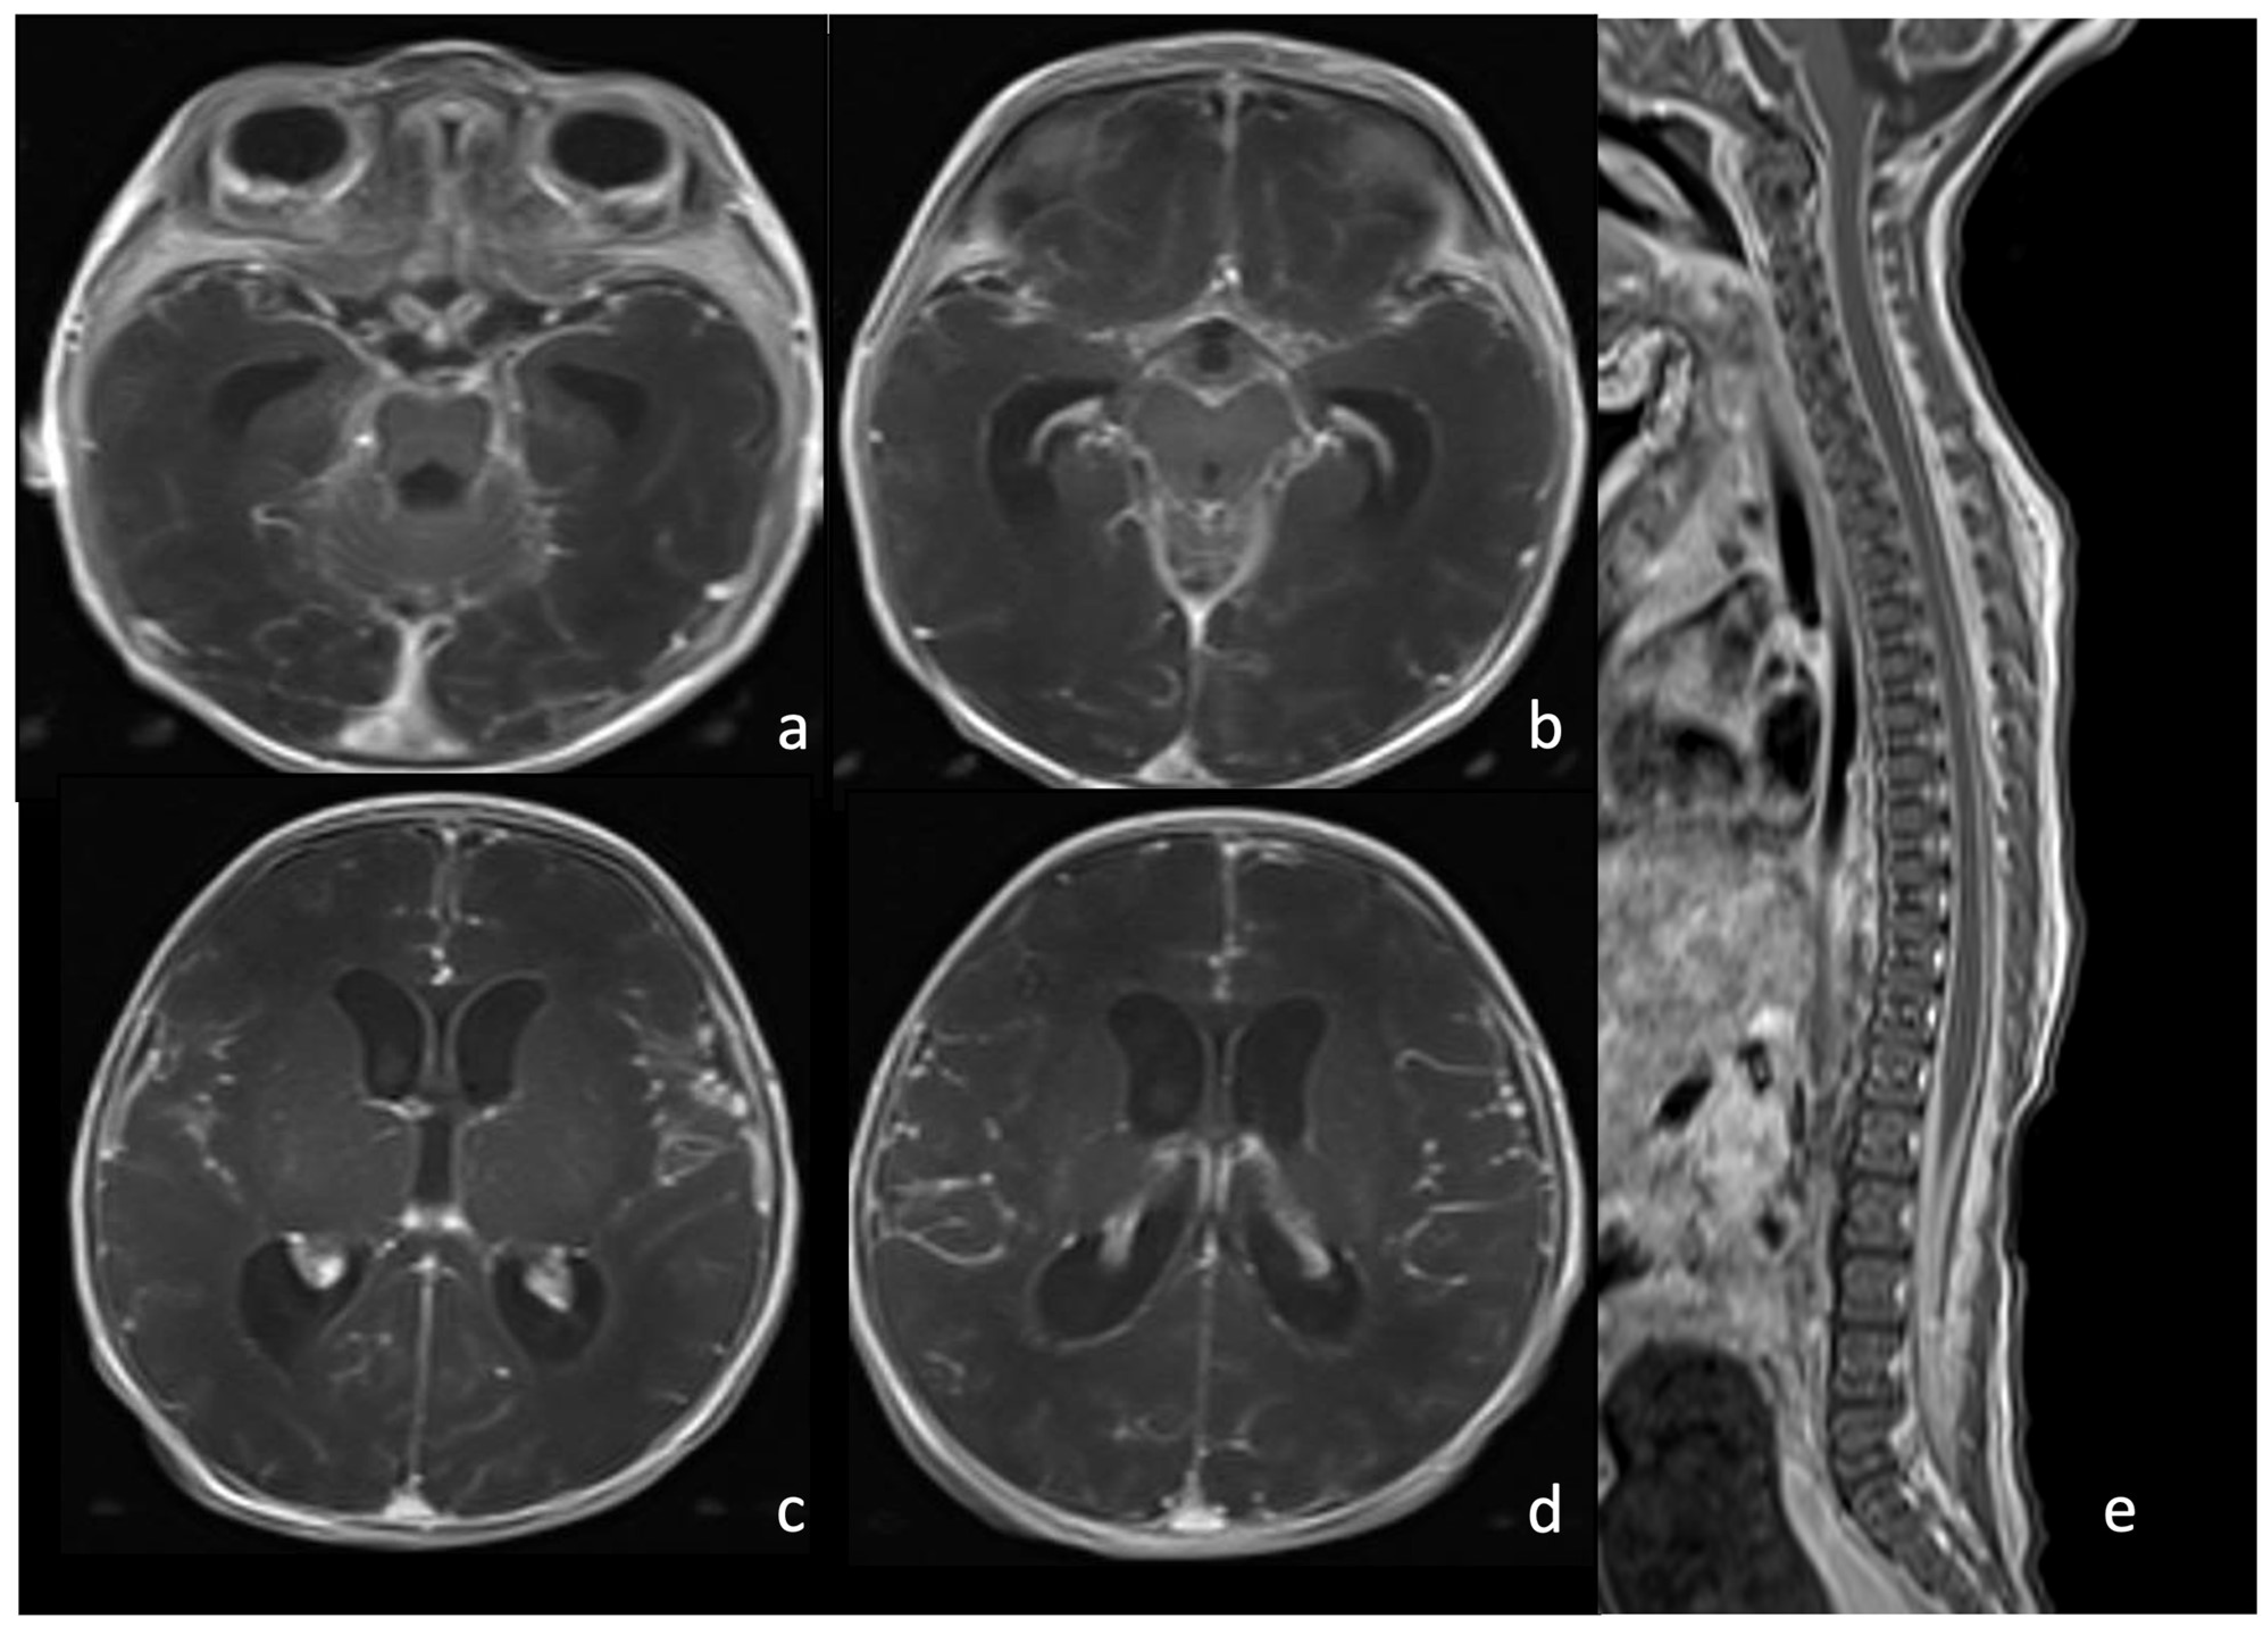

6.2. Infarcts

7.1. Group B Streptococcus

7.2. Listeria Monocytogenes